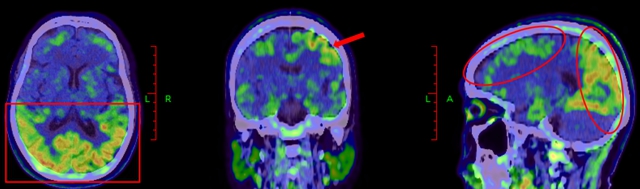

利用脑部影像学技术,如MRI可以发现特异区域的萎缩;PET-CT扫描,可以检测大脑中的异常蛋白质堆积或其他结构变化(见下图)。

阿尔茨海默病患者Tau蛋白PET,可显示大脑皮层广泛Tau蛋白沉积

以上图片由西南医科大学附属医院核医学科提供。